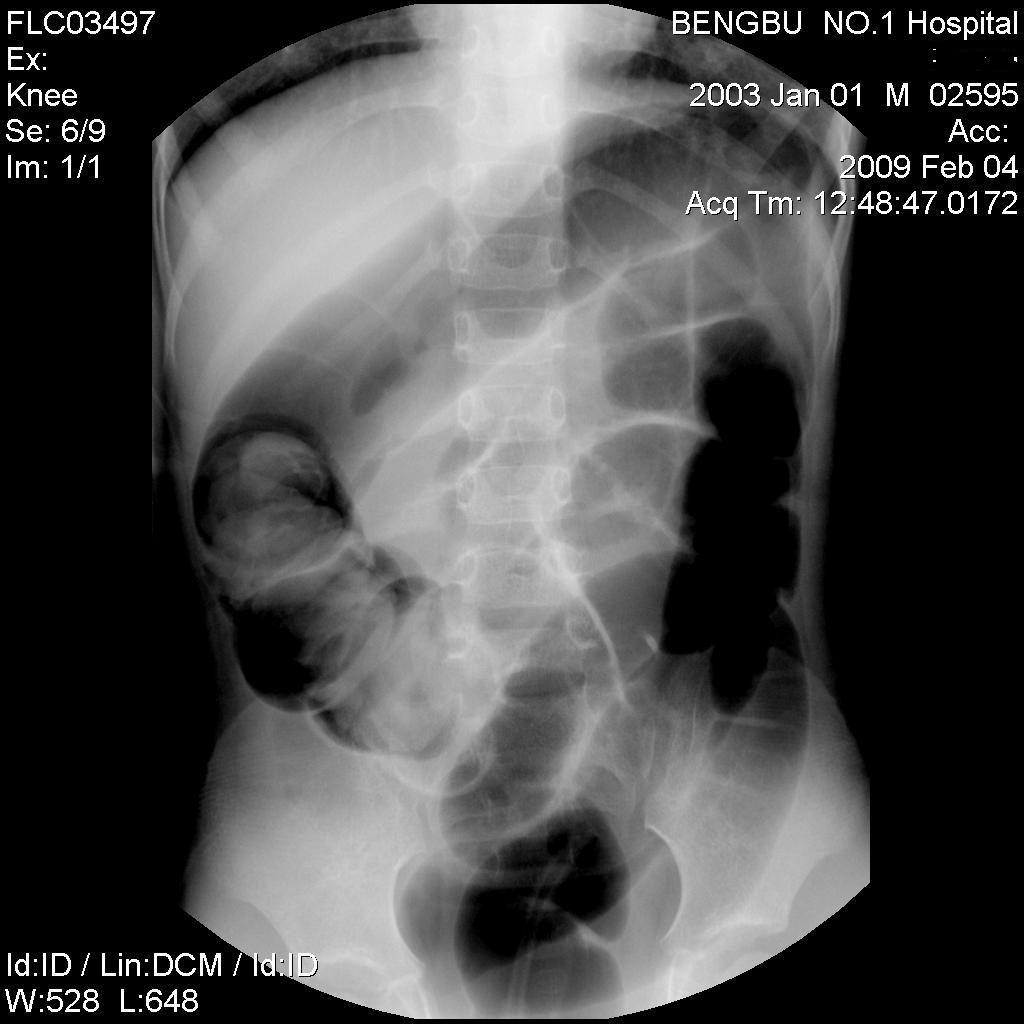

以下是引用杀毒软件在2009-2-5 14:51:00的发言:[br]提示肠梗阻----原因待查----大跨度肠绊---绞窄性可能性小---首选考虑---肠套叠或功能 性肠梗阻可能

以下是引用余辉在2009-2-5 8:52:00的发言:[br]考虑绞窄性肠梗阻,建议行钡剂灌肠检查

以下是引用随光逐影在2009-2-5 1:00:00的发言:[br]考虑肠套叠;建议行钡剂灌肠检查。